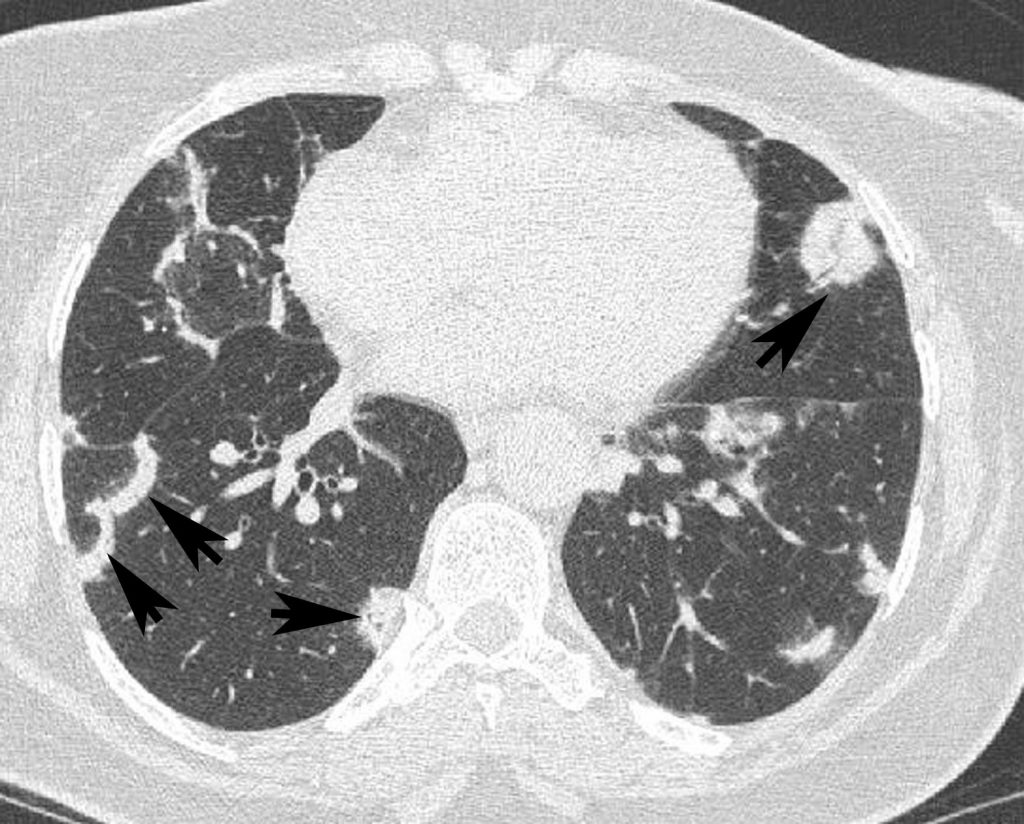

Fig. 97.4. Sarcoïdose.

Présence de micronodules dans la région moyenne des poumons, situés en région sous-pleurale, le long des septa interlobulaires (flèches) et le long des bronches (têtes de flèches).

Source : CERF, CNEBMN, 2022.